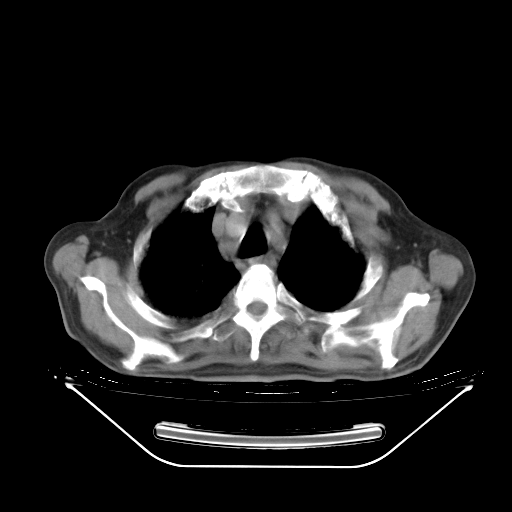

今天复查肺部CT,发现双肺广泛磨玻璃样改变。所以我把3月19日和5月9日相隔50天的肺部CT上传。请大家会诊。

2009年3月19日肺部CT片。

2009年3月19日肺部CT